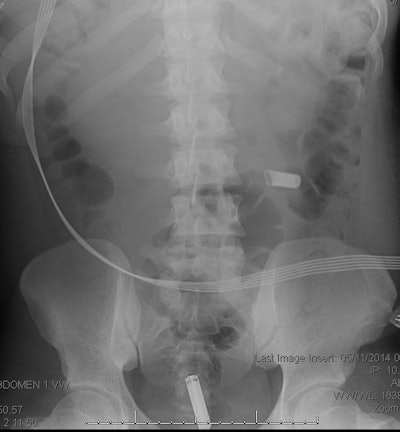

Foreign objects in the esophagus account for about 1,500 deaths per year in the U.S., and although most pass through without incident, about 10% to 20% require intervention. Children between the ages of 6 months and 6 years make up the majority of foreign body ingestion cases. Intentional ingestion of foreign bodies is more common in adults and tends to be associated with psychiatric illness, intellectual disability, substance abuse, incarceration, or drug smuggling ("body packing," or swallowing drug-filled packets), the researchers wrote.

In situations where a patient has aspirated a life-threatening object, bronchoscopy and laryngoscopy are standard diagnosis methods. But for nonlife-threatening items, two-view chest and neck x-rays can be used for the initial evaluation, the authors wrote. When it comes to detecting illegal drugs ingested by condom, balloon, or plastic, x-ray's performance can be variable, with false-negative rates as high as 23%; CT with intravenous contrast works better, according to Tseng and colleagues.